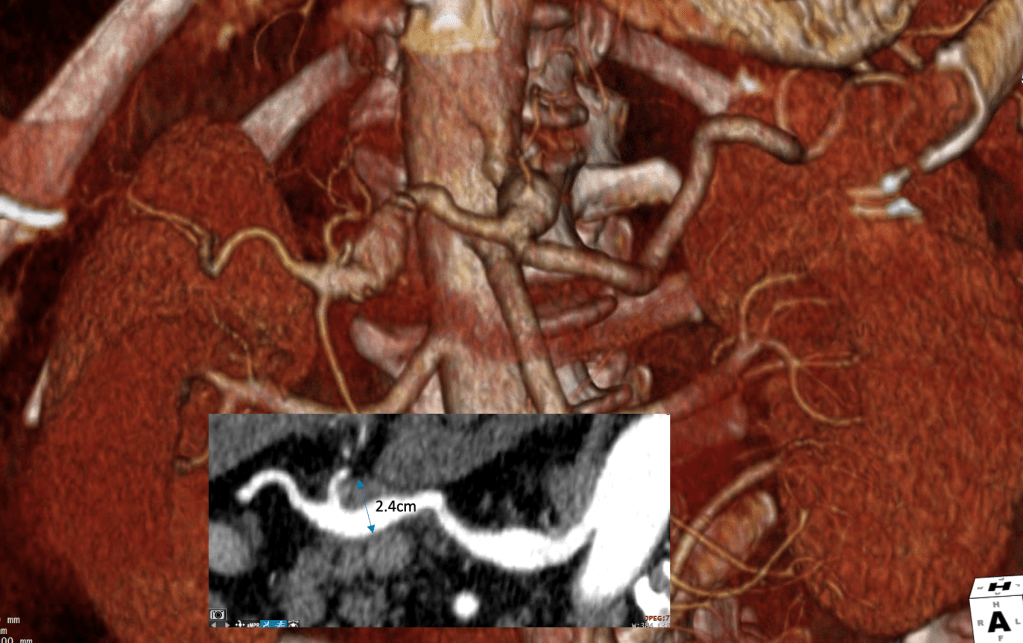

Common Hepatic Artery Aneurysm, 2.4cm with celiac axis ectasia to 14mm, median arcuate ligament compression of celiac axis

The CTA showed compression of the first centimeter of the celiac axis by the median arcuate ligament of the diaphragm and mild post-stenotic dilatation to 14mm. At the terminus of the common hepatic artery, where the hepatic bifurcated was a 2.4cm aneurysm with mural thrombus. With blood pressure control, his pain remitted.